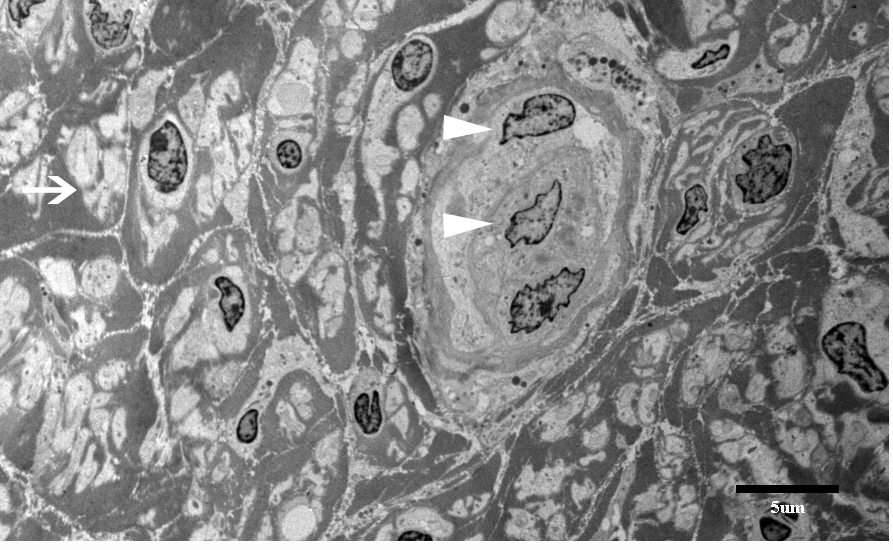

The nerve and muscle specimens from the lower extremity were received and processed per standard muscle and nerve workup protocols including enzyme histochemistry, special stains for nerve and muscle, nerve teasing, and electron microscopy. H&E stained sections of the nerve biopsy show cross sections of sural nerve and surrounding connective tissues (Figure 1A). Blood vessels show no evidence of vasculitis, and Congo red stain displays no evidence of amyloidosis. There is significant fibrosis of the peri-, epi -or endoneurium observed. These are best highlighted with trichrome stain (Figure 1D). Trichrome also shows no large myelinated fibers. A neurofilament immunostain displays evenly distributed and moderately diminished complement of axons (Figure 1B). One micron thick, toluidine blue stained sections display cross sections of several nerve fascicles. This stain shows a complete absence of thickly myelinated fibers (Figure 1C). No supernumerary Schwann cell accumulations are seen. Endoneurial vessels have enlarged endothelial cells. Ultrastructural analysis of these sections confirms the observations seen on thick sections (Figure 2). There is no discernible thick or thin myelin present around axons. Unmyelinated fibers have loosely arranged membranes around them, and Schwann cell nuclei are present. No supernumerary Schwann cells are present (Figure 2). The tease preparation displays strands of fibrous tissue without any discernable myelinated fibers.

Figure 2 Ultrastructure of sural nerve shows no discernible thick or thin myelination present around axons (Single arrow). Unmyelinated fibers have loosely arranged membrane around them and Schwann cell nuclei are present (arrow head). No supernumerary Schwann cell onion bulb formations are seen. (X5000).